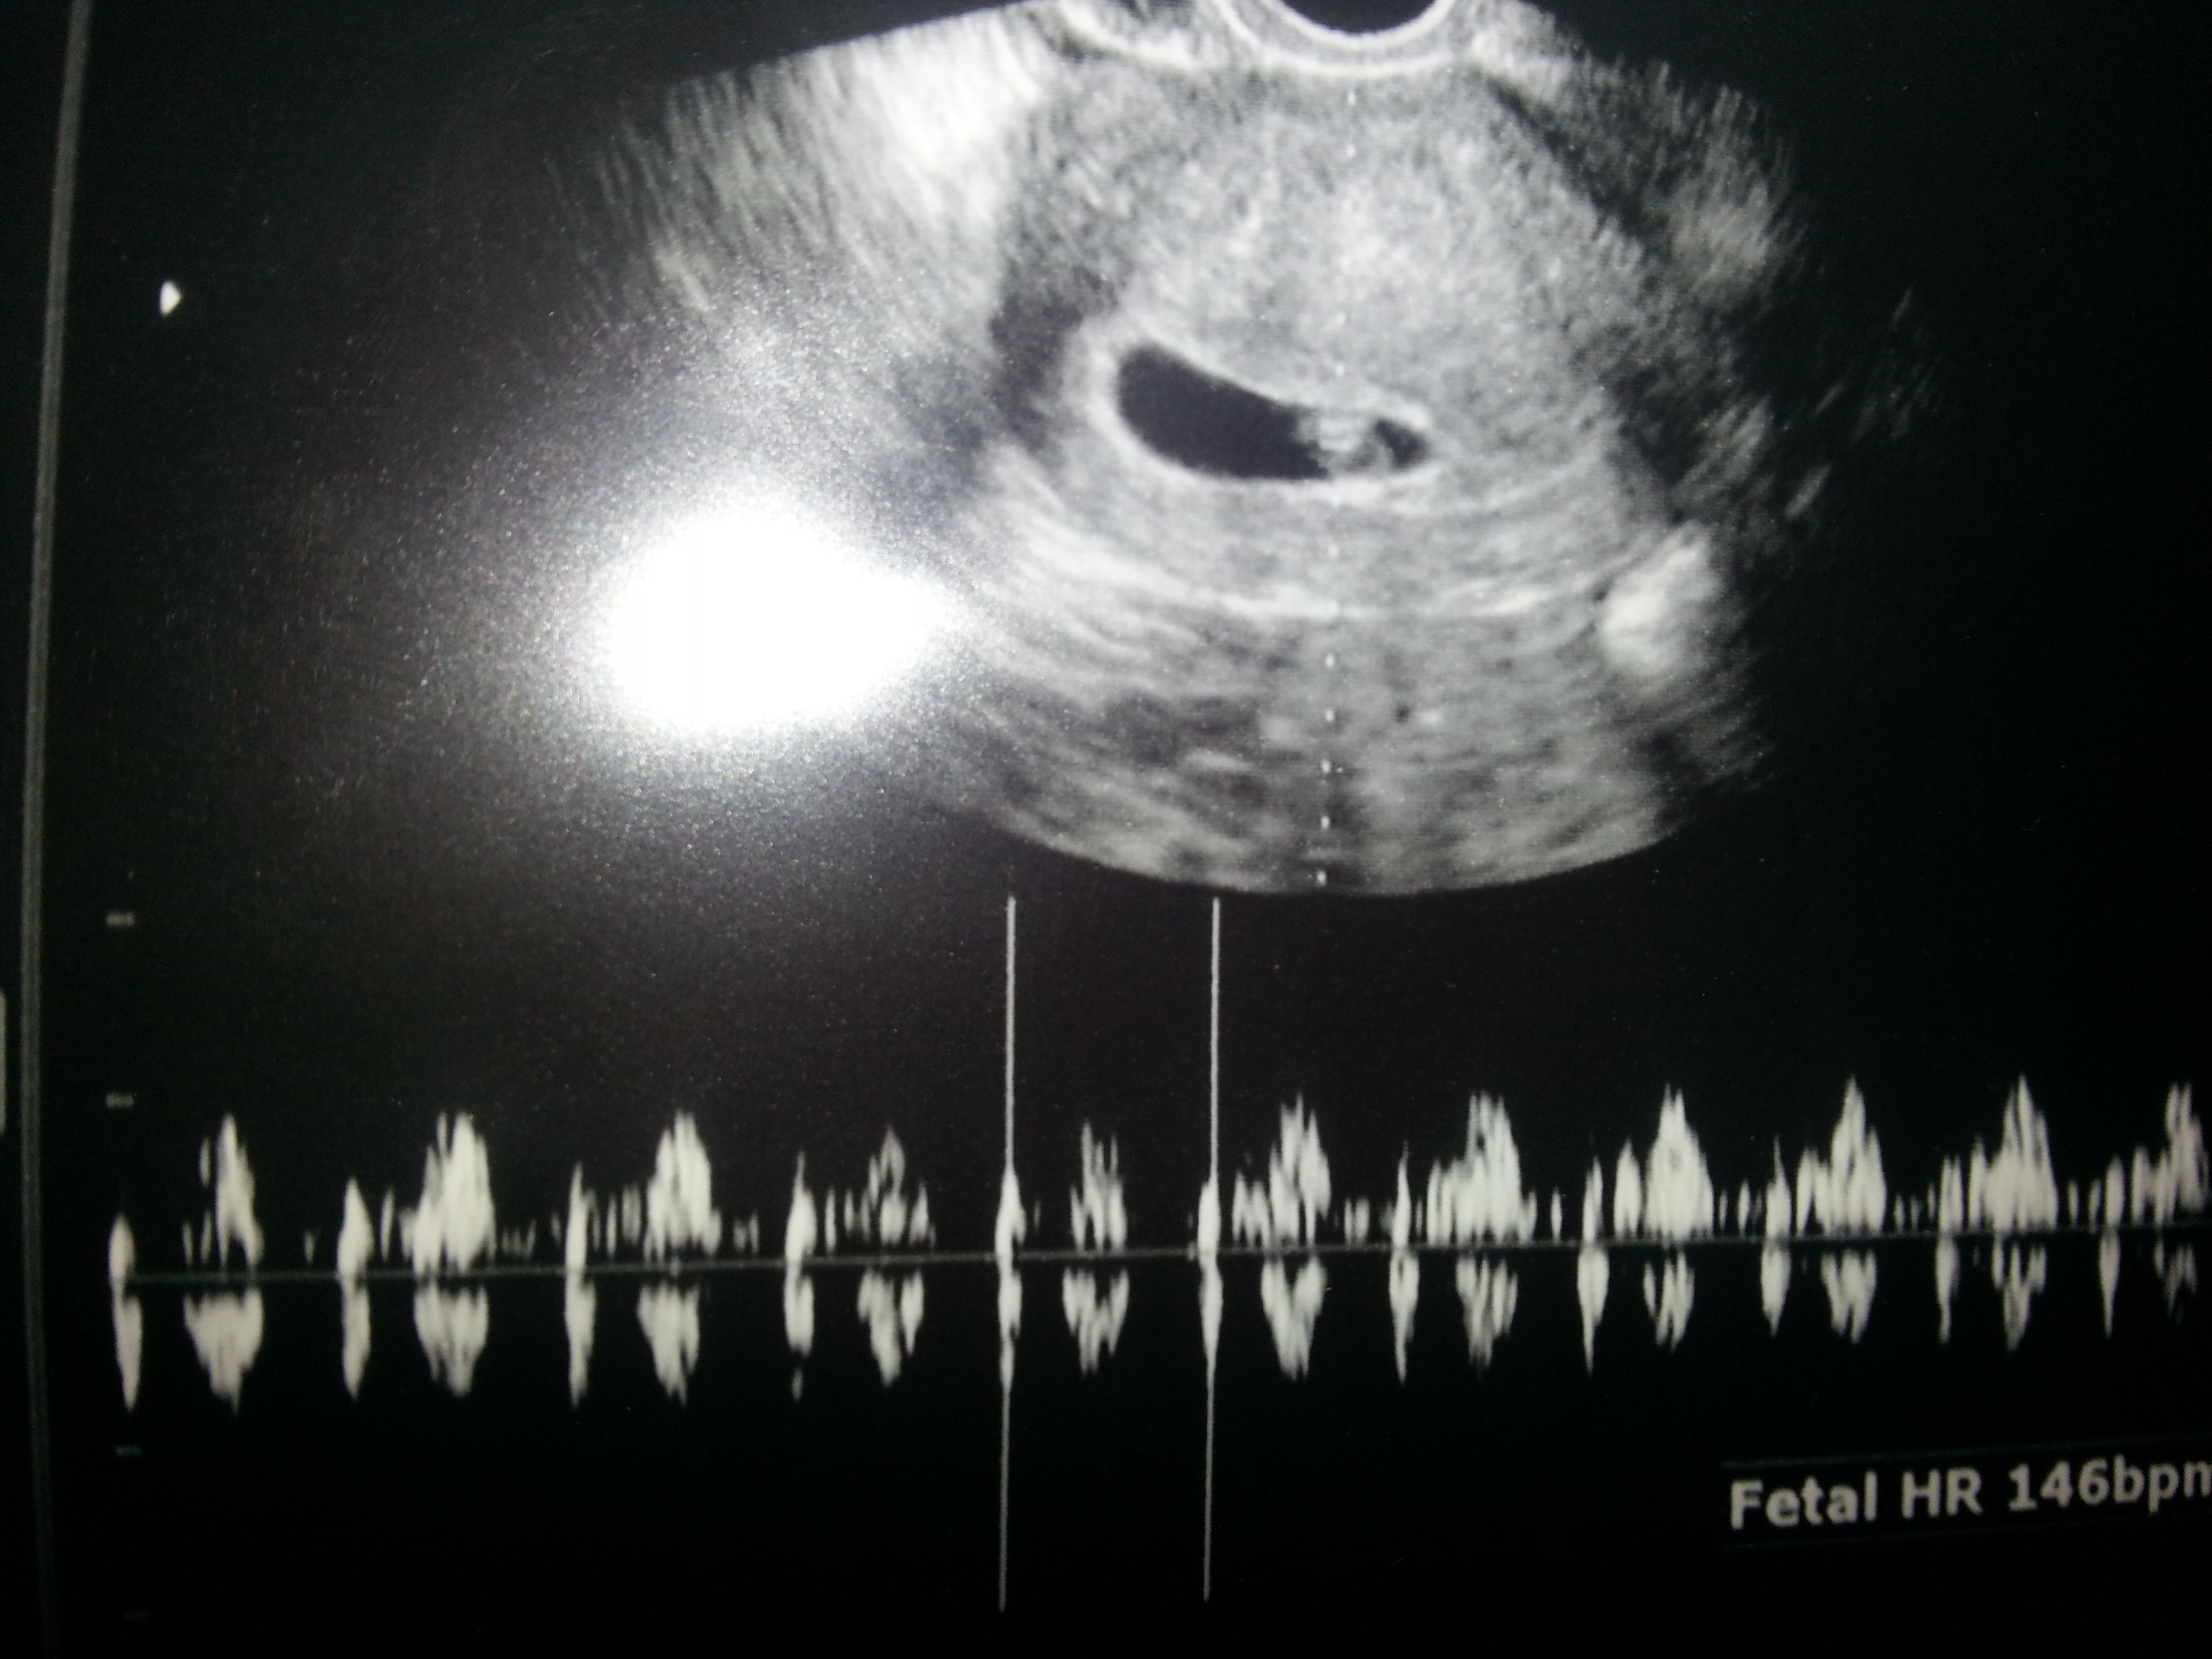

*update* well needless to say I was completely shocked at my appt. Not only was our bean in there and measuring perfectly...we got to hear his/her beautiful hb going at 146bpm. Dh and I started crying and just couldnt believe it. I will NEVER be using a hpt again to see how pg I am. Here is our u/s from today! Thank you so much for the support ladies!

image